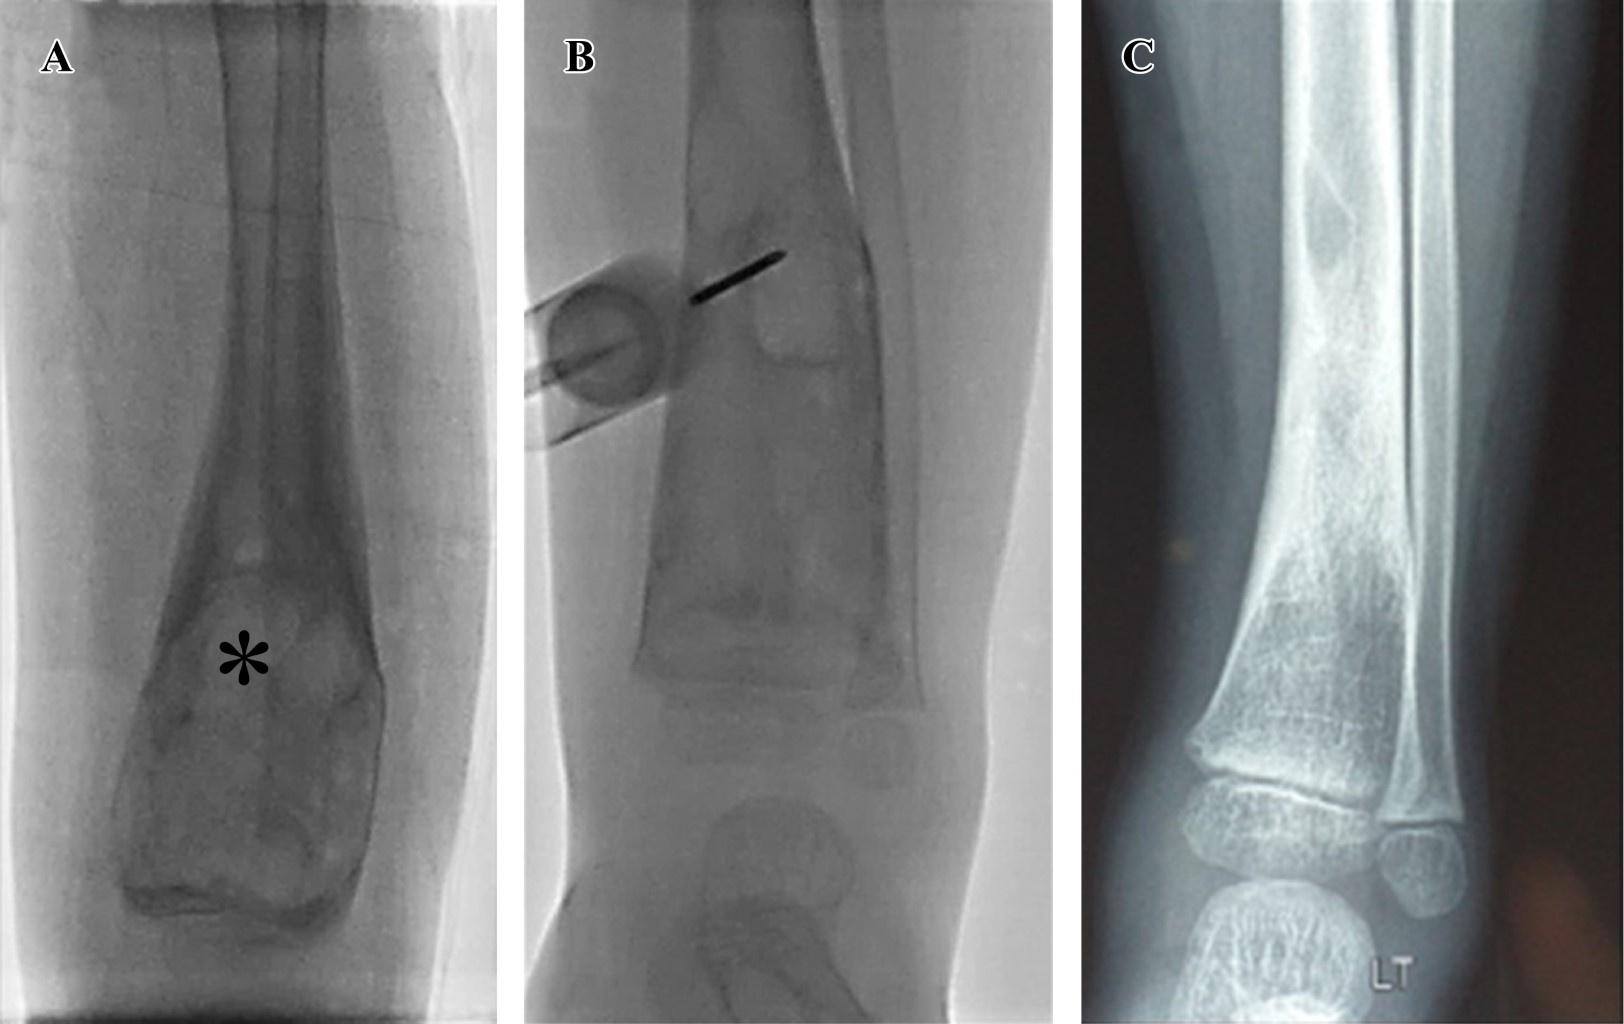

En los casos uno (Figura 1), cuatro, cinco, seis, siete y nueve se inyectaron 5 ml de polidocanol 3% en todas las sesiones. El primer paciente había recibido cirugía con curetaje óseo de la lesión un año antes por presentar recidiva del QOA, por lo que se optó por tratarle con escleroterapia. Al segundo paciente, en otra institución se le había realizado embolización de arterias aferentes del QOA, misma que fue inefectiva, motivo por el que se le realizó curetaje e injerto óseo; en menos de un año de seguimiento se evidenció recurrencia del QOA (Figura 2), razón por la cual se le indicó tratamiento con escleroterapia, recibió 5 ml de polidocanol 3% en la primera dosis y 10 ml en las dosis siguientes. En el tercero (Figura 3) y octavo pacientes se inyectaron 10 ml de la sustancia esclerosante en todas las sesiones. Número total de procedimientos: 44, cantidad de procedimientos por paciente: promedio 4.9 (DE: ± 2.0). Intervalo de dosis: promedio 11.54 semanas (DE: ± 14.57).

Figura 3